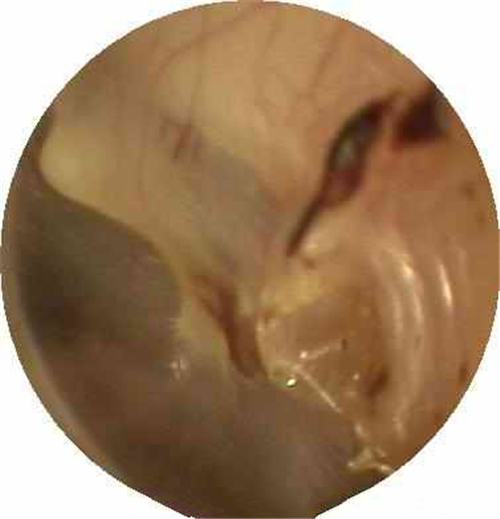

左耳鼓膜穿孔